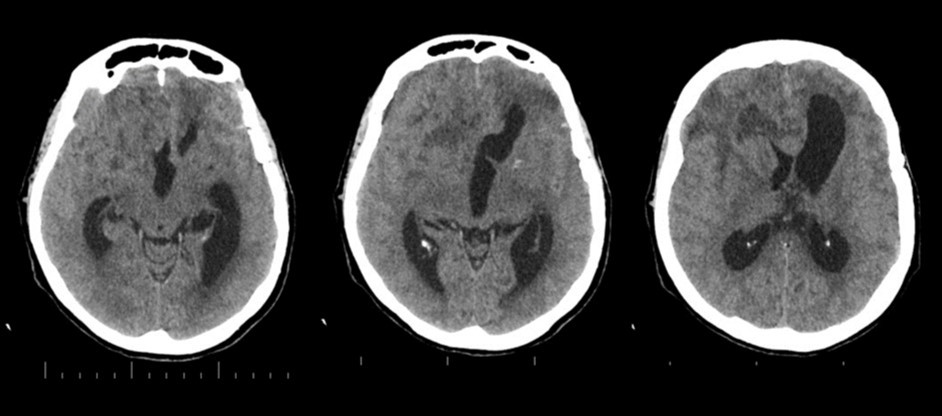

The follow-up CT scan made two weeks later showed a mild ventricular enlargement and persistent density alterations in the frontal region (Figure 2) that were interpreted as normal. Once discharged at home, the patient developed progressive disorientation that finally let her refer to our hospital for consult four months after aneurysm clipping. The cerebral CT we performed showed further ventricular growth, and a tumor-like image in the right frontal lobe (Figure 3). She was admitted to our ward and underwent a contrast-MRI that confirmed the suspicion of aggressive intra-axial neoplasm (Figure 4). The week after, under general anesthesia we performed a right craniotomy and removed a large part of the tumor, sparing the portion going through the corpus callosum (Figure 5). During convalescence the patient had few epileptic attacks, treated with drugs. A mild cognitive impairment persisted after surgery, without focal motor deficits. The gait, limited and unstable since the SAH, remained poor and the patient never walked again after the operation. The histological examination indicated a WHO grade IV glioma: IDH1-p53 negative glioblastoma. The patient and her relatives refused a ventriculo-peritoneal shunt after knowing this unfortunate diagnosis. Transferred to rehabilitation, the woman made just a short low-dose chemotherapy cycle and finally died four months after tumor resection.

Figure 3.4 months non-contrast CT scan. Ventricles are dilated. A mass clearly affects the right frontal and midline region